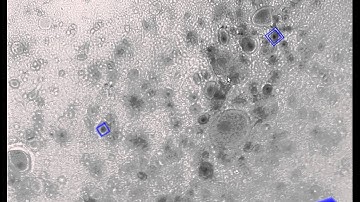

Demonstration Video for "Artificial Defocus for Displaying Markers in Microscopy Z-Stacks"